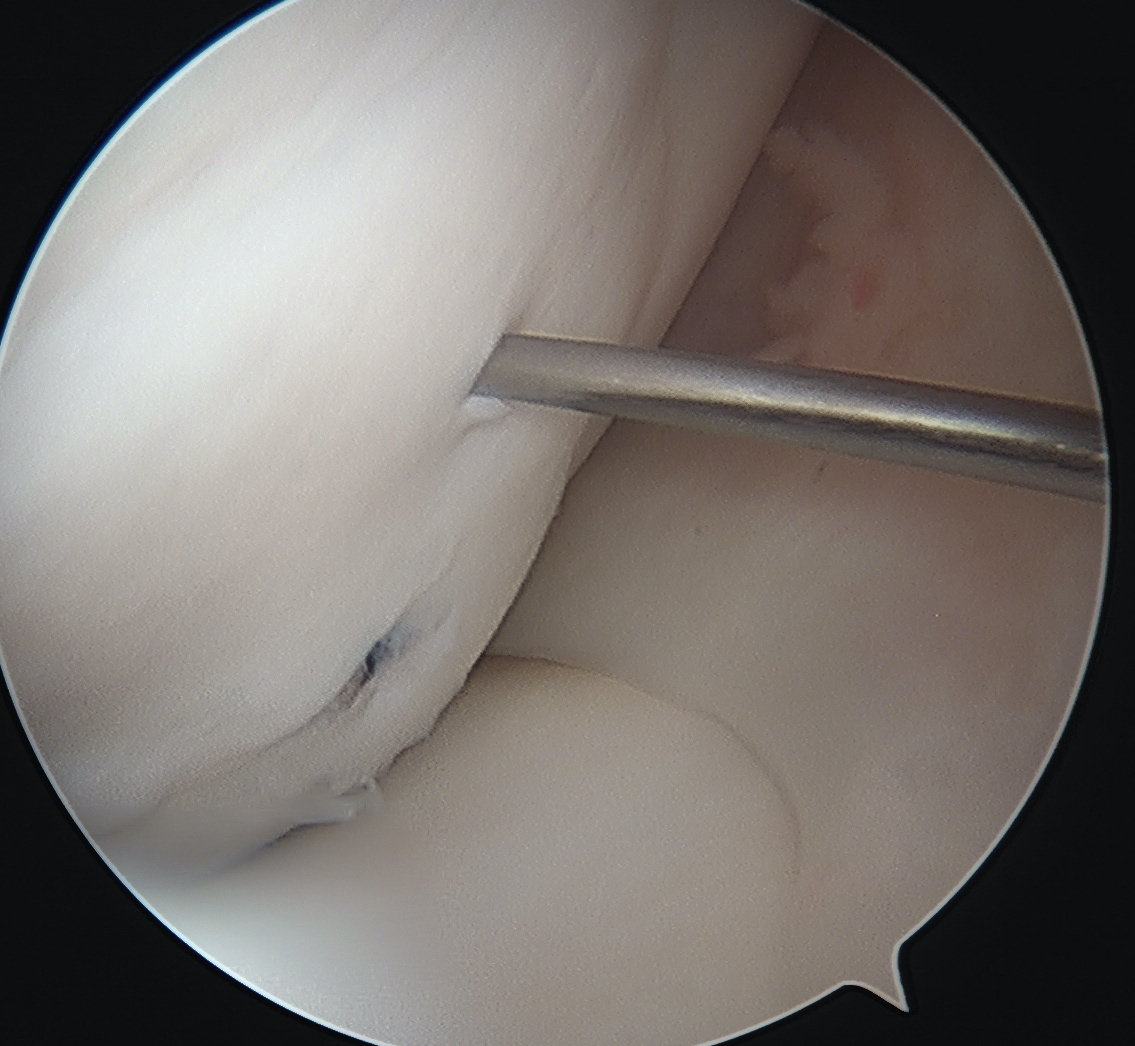

Flex and extend knee to place inferior / superior screws

- flex and extend knee to place inferior / superior screws

Inferior screw Superior screw